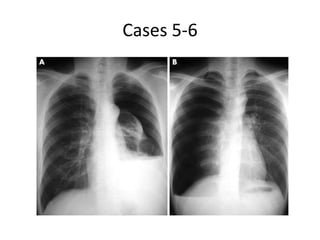

Case 2 CXR

Cases 5-6